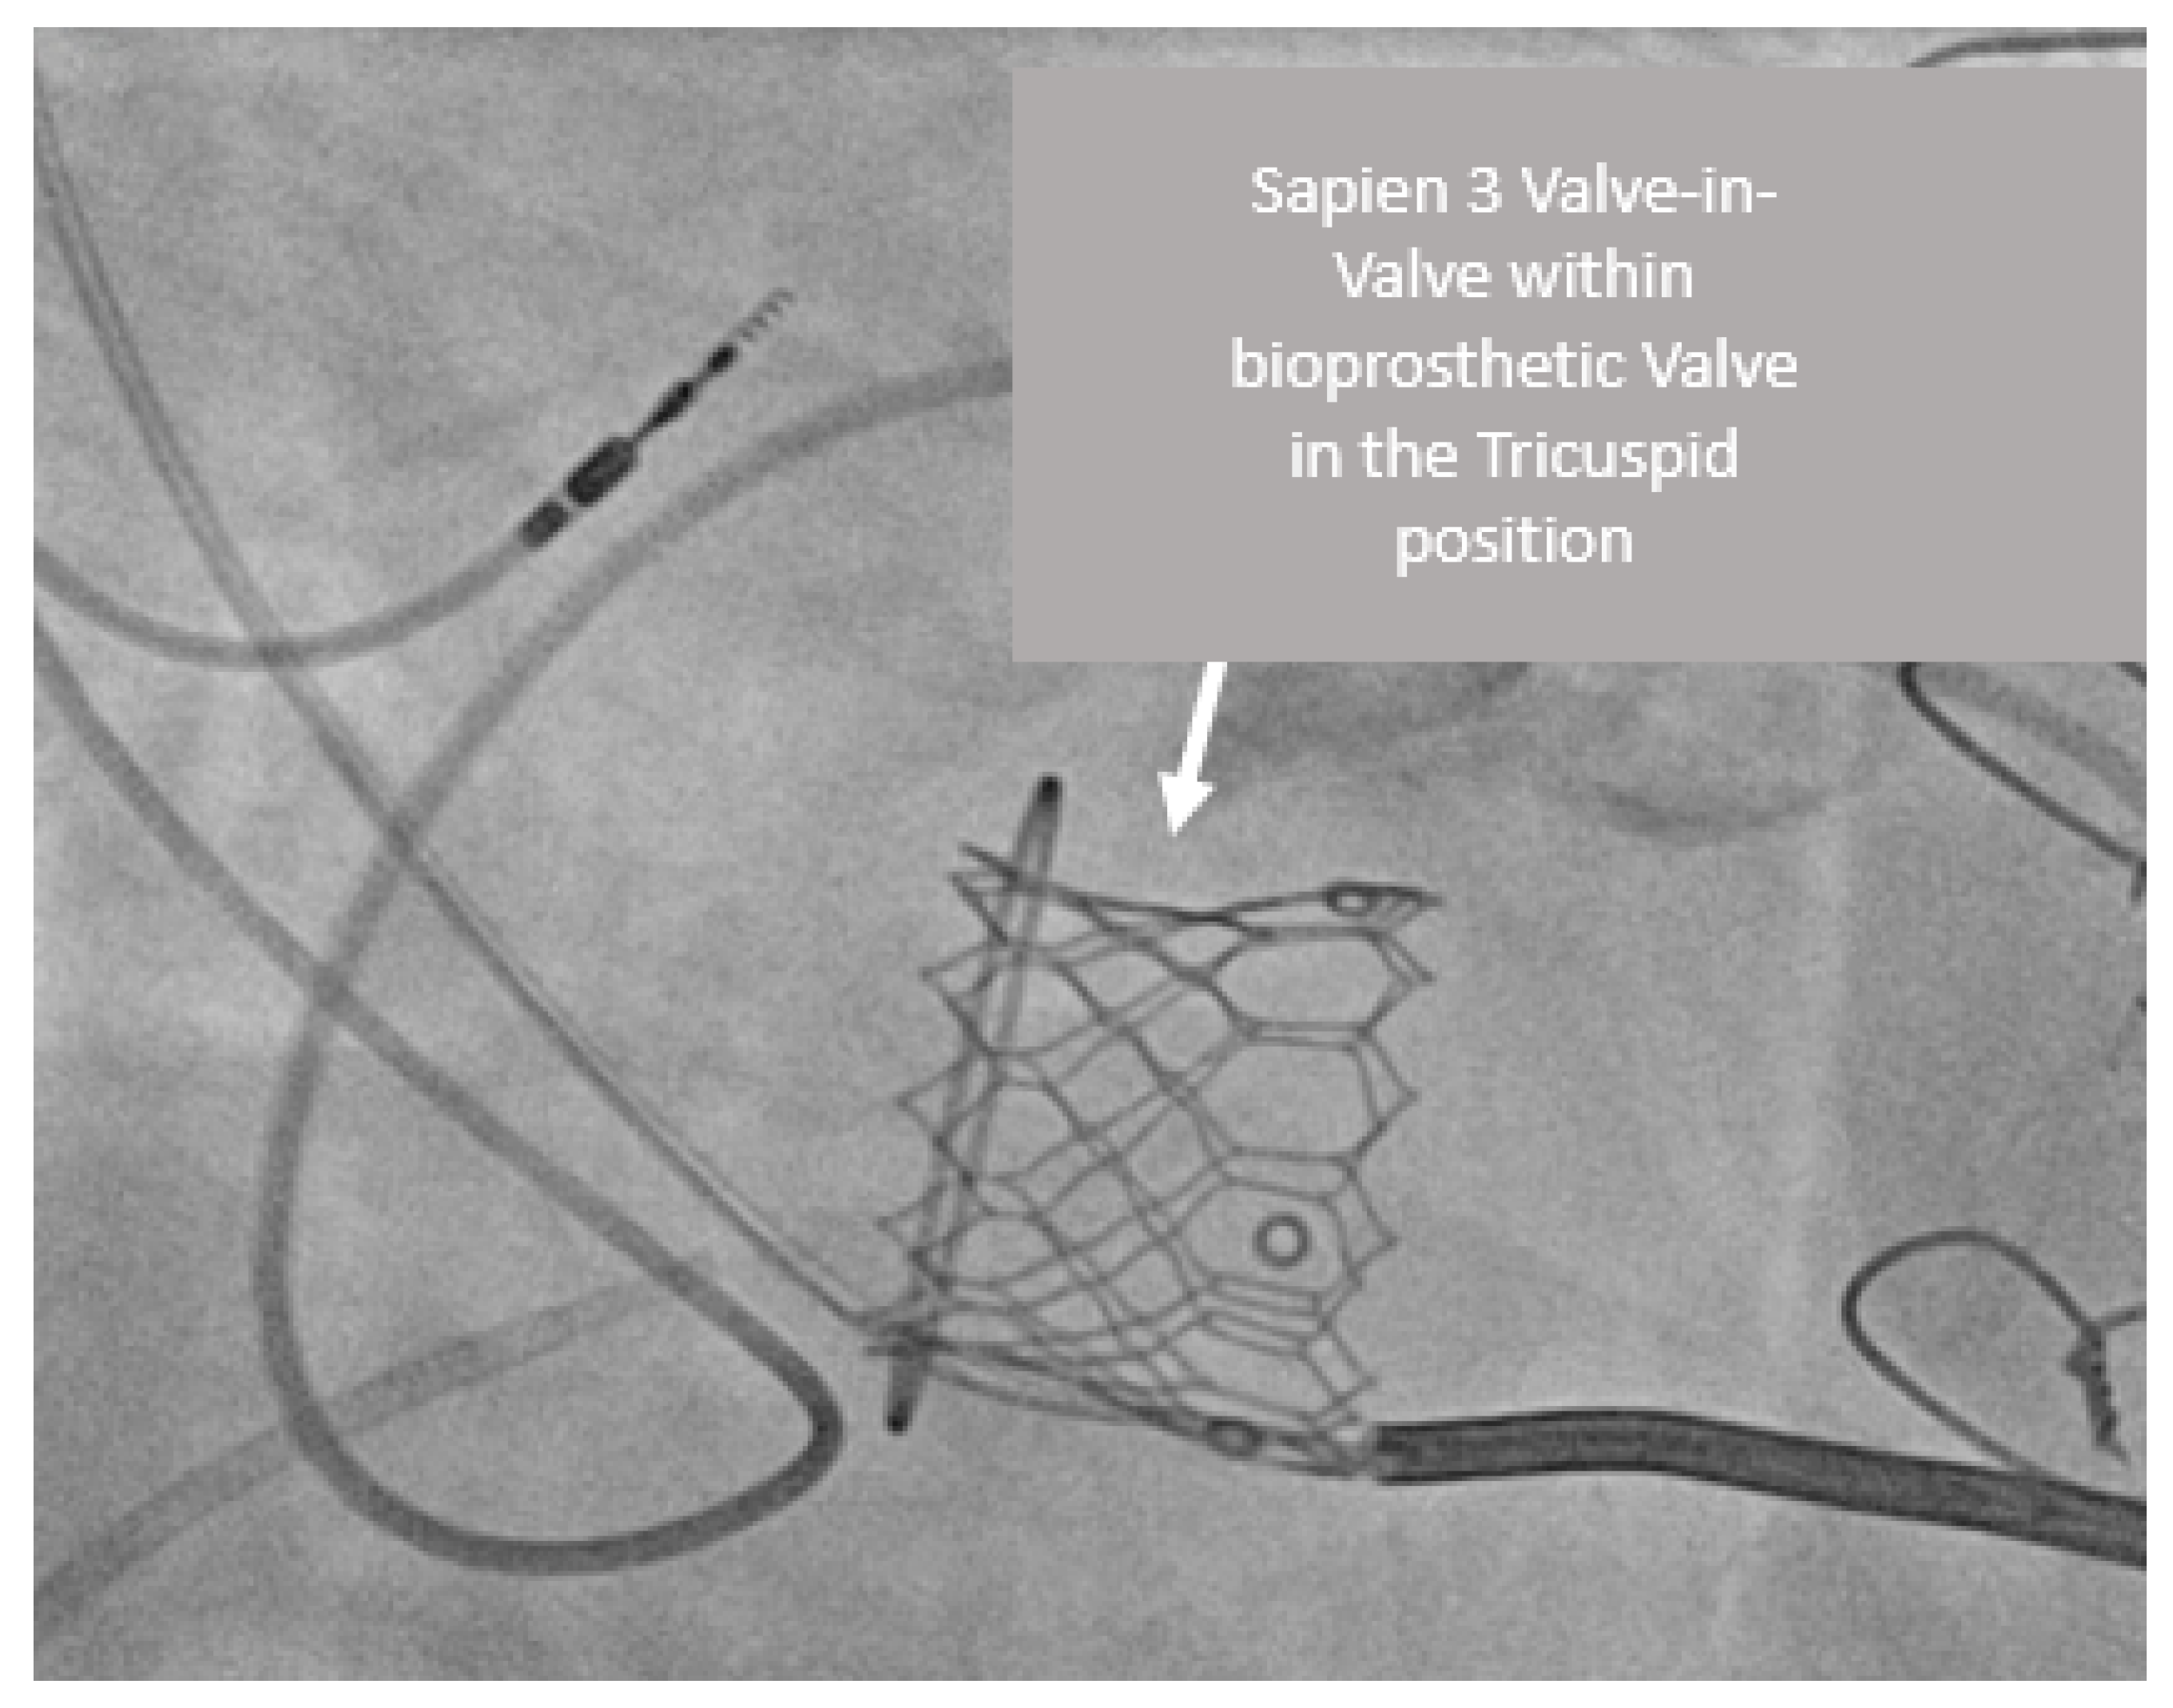

3.3. Case 3

| 5th | Female | Ebstein anomaly with 2 previous tricuspid valve replacements and bioprosthesis SVD | 2 | 23 | Pulmonary | Mixed | VIV | None |